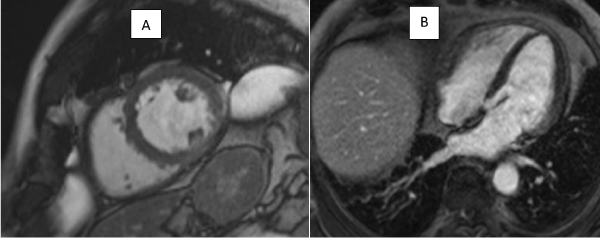

A CMR 6 months later shows resolution of the lesion but persisting LGE in the left circumflex territory (Figures 4 and 5).

Given the transience of the left ventricular abnormality and its location, it was concluded that the culprit coronary lesion in the first instance was likely to have been the left circumflex: the CMR abnormalities represent a left ventricular aneurysm and a pericardial effusion related to post cardiac injury (Dressler’s) syndrome (Figures 6 and 7).

Figure 7: LGE contrast imaging showing fixed perfusion defect in basal lateral wall in follow up study 6 months later.

Figures 6: Still images from 6 monthly follow up scan from SSFP cine sequences showing resolution of left ventricular aneurysm